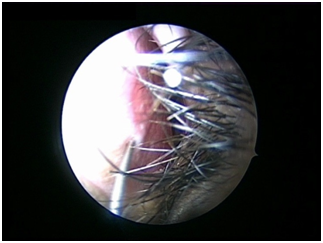

Nasal Endoscopy is done to assess the septal deviation and spurs (Figure 1) ( Figure 2). Septal infiltration is carried out with a solution of 2% Xylocaine with 1: 100,000 adrenaline in the sub-mucosal plane. It is given with a single prick at the inferior most part of the nasal septum at the junction of the septum with the floor of the nasal cavity anterior to the mucocutaneous junction. The infiltration is given at the same point on both the sides (Figure 3). The incision is always given on the deviated side. It is given anterior to the mucocutaneous junction because the skin present at that place is thick and chance of a tear of the flap is less (Figure 4). The mucoperichondrial flap is raised on the deviated side with a Freer’s elevator strictly under vision. The flap is not to be raised beyond the deviated part because the part of the septum posterior to the deviation is not under direct vision (Figure 5) (Figure 6). The caudal end of the septum is then palpated and an incision is given on the cartilage 1cm behind the columella. This 1cm of the cartilage is saved to prevent post operative tip deformities (Figure 7). The cartilage is sliced and the opposite side is entered, the mucoperichondrial flap of the opposite side is then elevated with a Freer’s elevator. A cut is given in the septal cartilage as high as possible. A septal window is created and a Ballenger’s swivel knife is taken and lodged in the place where the cartilage was cut. Creation of a septal window thus increases the area of exposure (Figure 8) (Figure 9). The flap on the non-deviated side is elevated till the bony-cartilaginous junction.

Figure 1 Deviation of septum to left side.

Figure 2 Spur present towards left side.